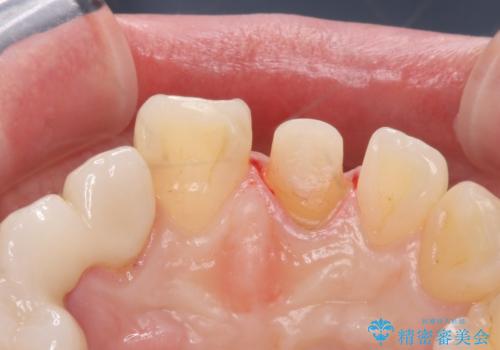

- 前歯の被せ物のやり替えを希望して来院されました。

再根管治療の後、審美性の良いジルコニアクラウンをセットしていきます。